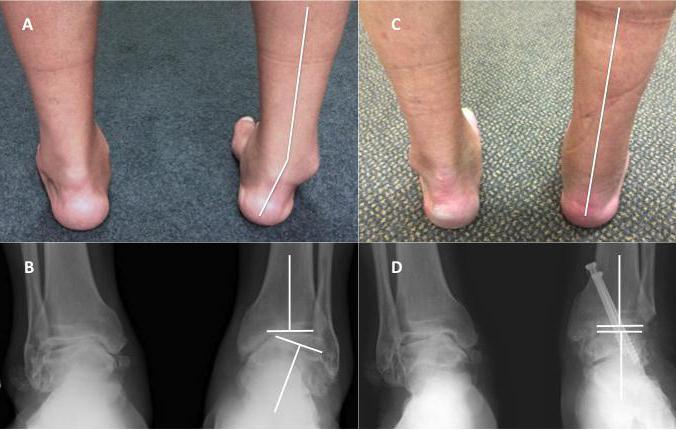

Лечение

Терапия болезни Хагланда-Шинца преимущественно консервативная, в редких случаях показано оперативное вмешательство. Лечебные методы могут немного отличаться в зависимости от состояния ребенка и тяжести симптомов. Однако каждому пациенту рекомендуется снизить нагрузку на ноги и использовать ортопедические приспособления – стельки, супинаторы или подпяточники.

Если болевой синдром носит выраженный характер, то конечность кратковременно фиксируют гипсом. Для уменьшения болевых ощущений назначаются противовоспалительные, обезболивающие и сосудорасширяющие (вазодилататорные) средства, а также витамины группы В.

Разгрузить стопу, и пяточный бугор в частности, помогает ортопедический тутор с разгрузочным стременем, который надевается на голень и стопу. Это устройство фиксирует ногу в согнутом положении. В некоторых случаях необходимо применение дополнительных приспособлений, предотвращающих разгибание ноги в коленном суставе и фиксирующих его в положении сгибания.

Немаловажное значение имеет обувь, которая должна иметь каблук средней высоты и ортопедическую вкладку-стельку с внутренним и внешним сводом. Лучше всего сделать такую стельку на заказ с учетом индивидуальных параметров стопы.